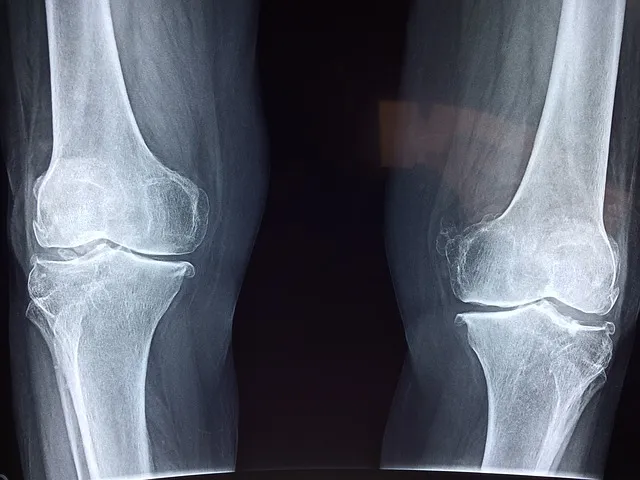

영상 검사

X-레이, MRI, CT 스캔 등의 영상 검사를 통해 무릎 관절 내 구조를 자세히 살펴볼 수 있습니다. 이를 통해 연골 손상, 인대 손상, 관절염 등의 상태를 진단할 수 있습니다.